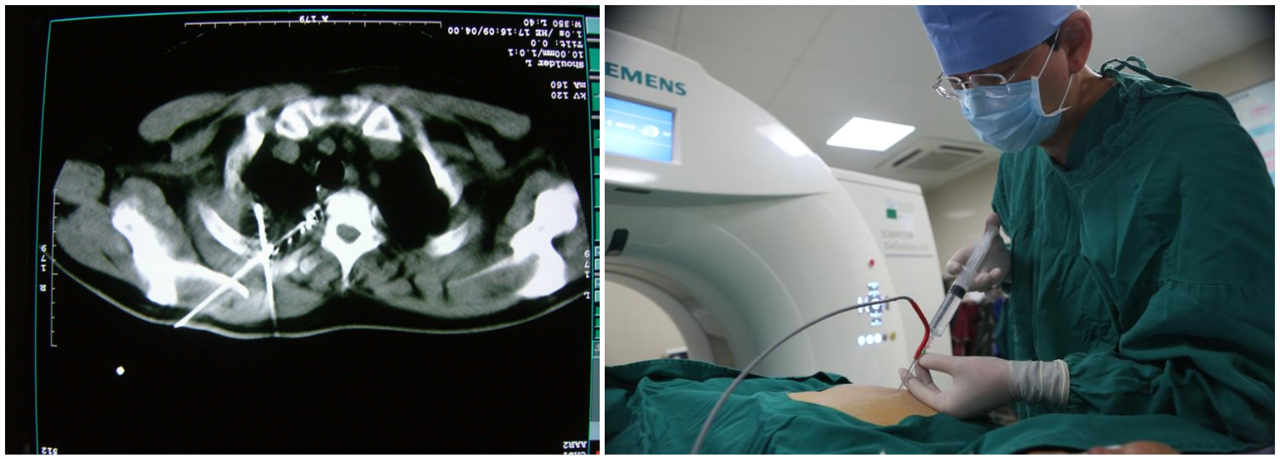

手術(shù)中

術(shù)后魯叔感覺良好,就想趕著回家過年,經(jīng)過醫(yī)生的評估,魯叔于1月15日辦理出院?!拔乙婚_始很害怕會因為過年放假而被醫(yī)院拒收,沒想到我的就診反而讓不少醫(yī)護人員改簽了車票,他們用自己回家過年的時間來悉心照顧我。”魯叔很感謝自己沒有被放棄還活了下來。